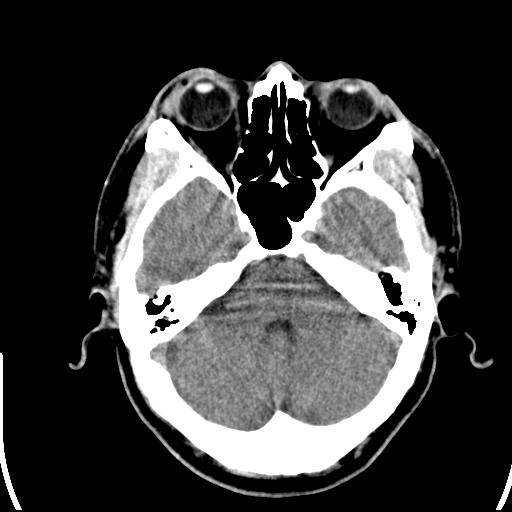

标题: CT25435:头皮下高密度影???

头皮下高密度结节影???临床上在老年男性比较常见。大家看看是什么?成因是? 本例患者,男性,51岁。外伤来诊。无染发史及发根植入史。